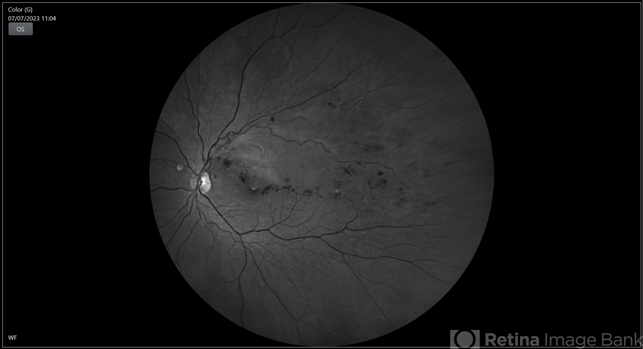

- BRVO

- BRVO, branch retinal vein occlusion (BRVO), non-perfused branch retinal vein occlusion (BRVO)

- 43-year-old woman presented with left eye old STBRVO with chronic CME of duration 6month showing ring shaped collaterals more evident on red free image